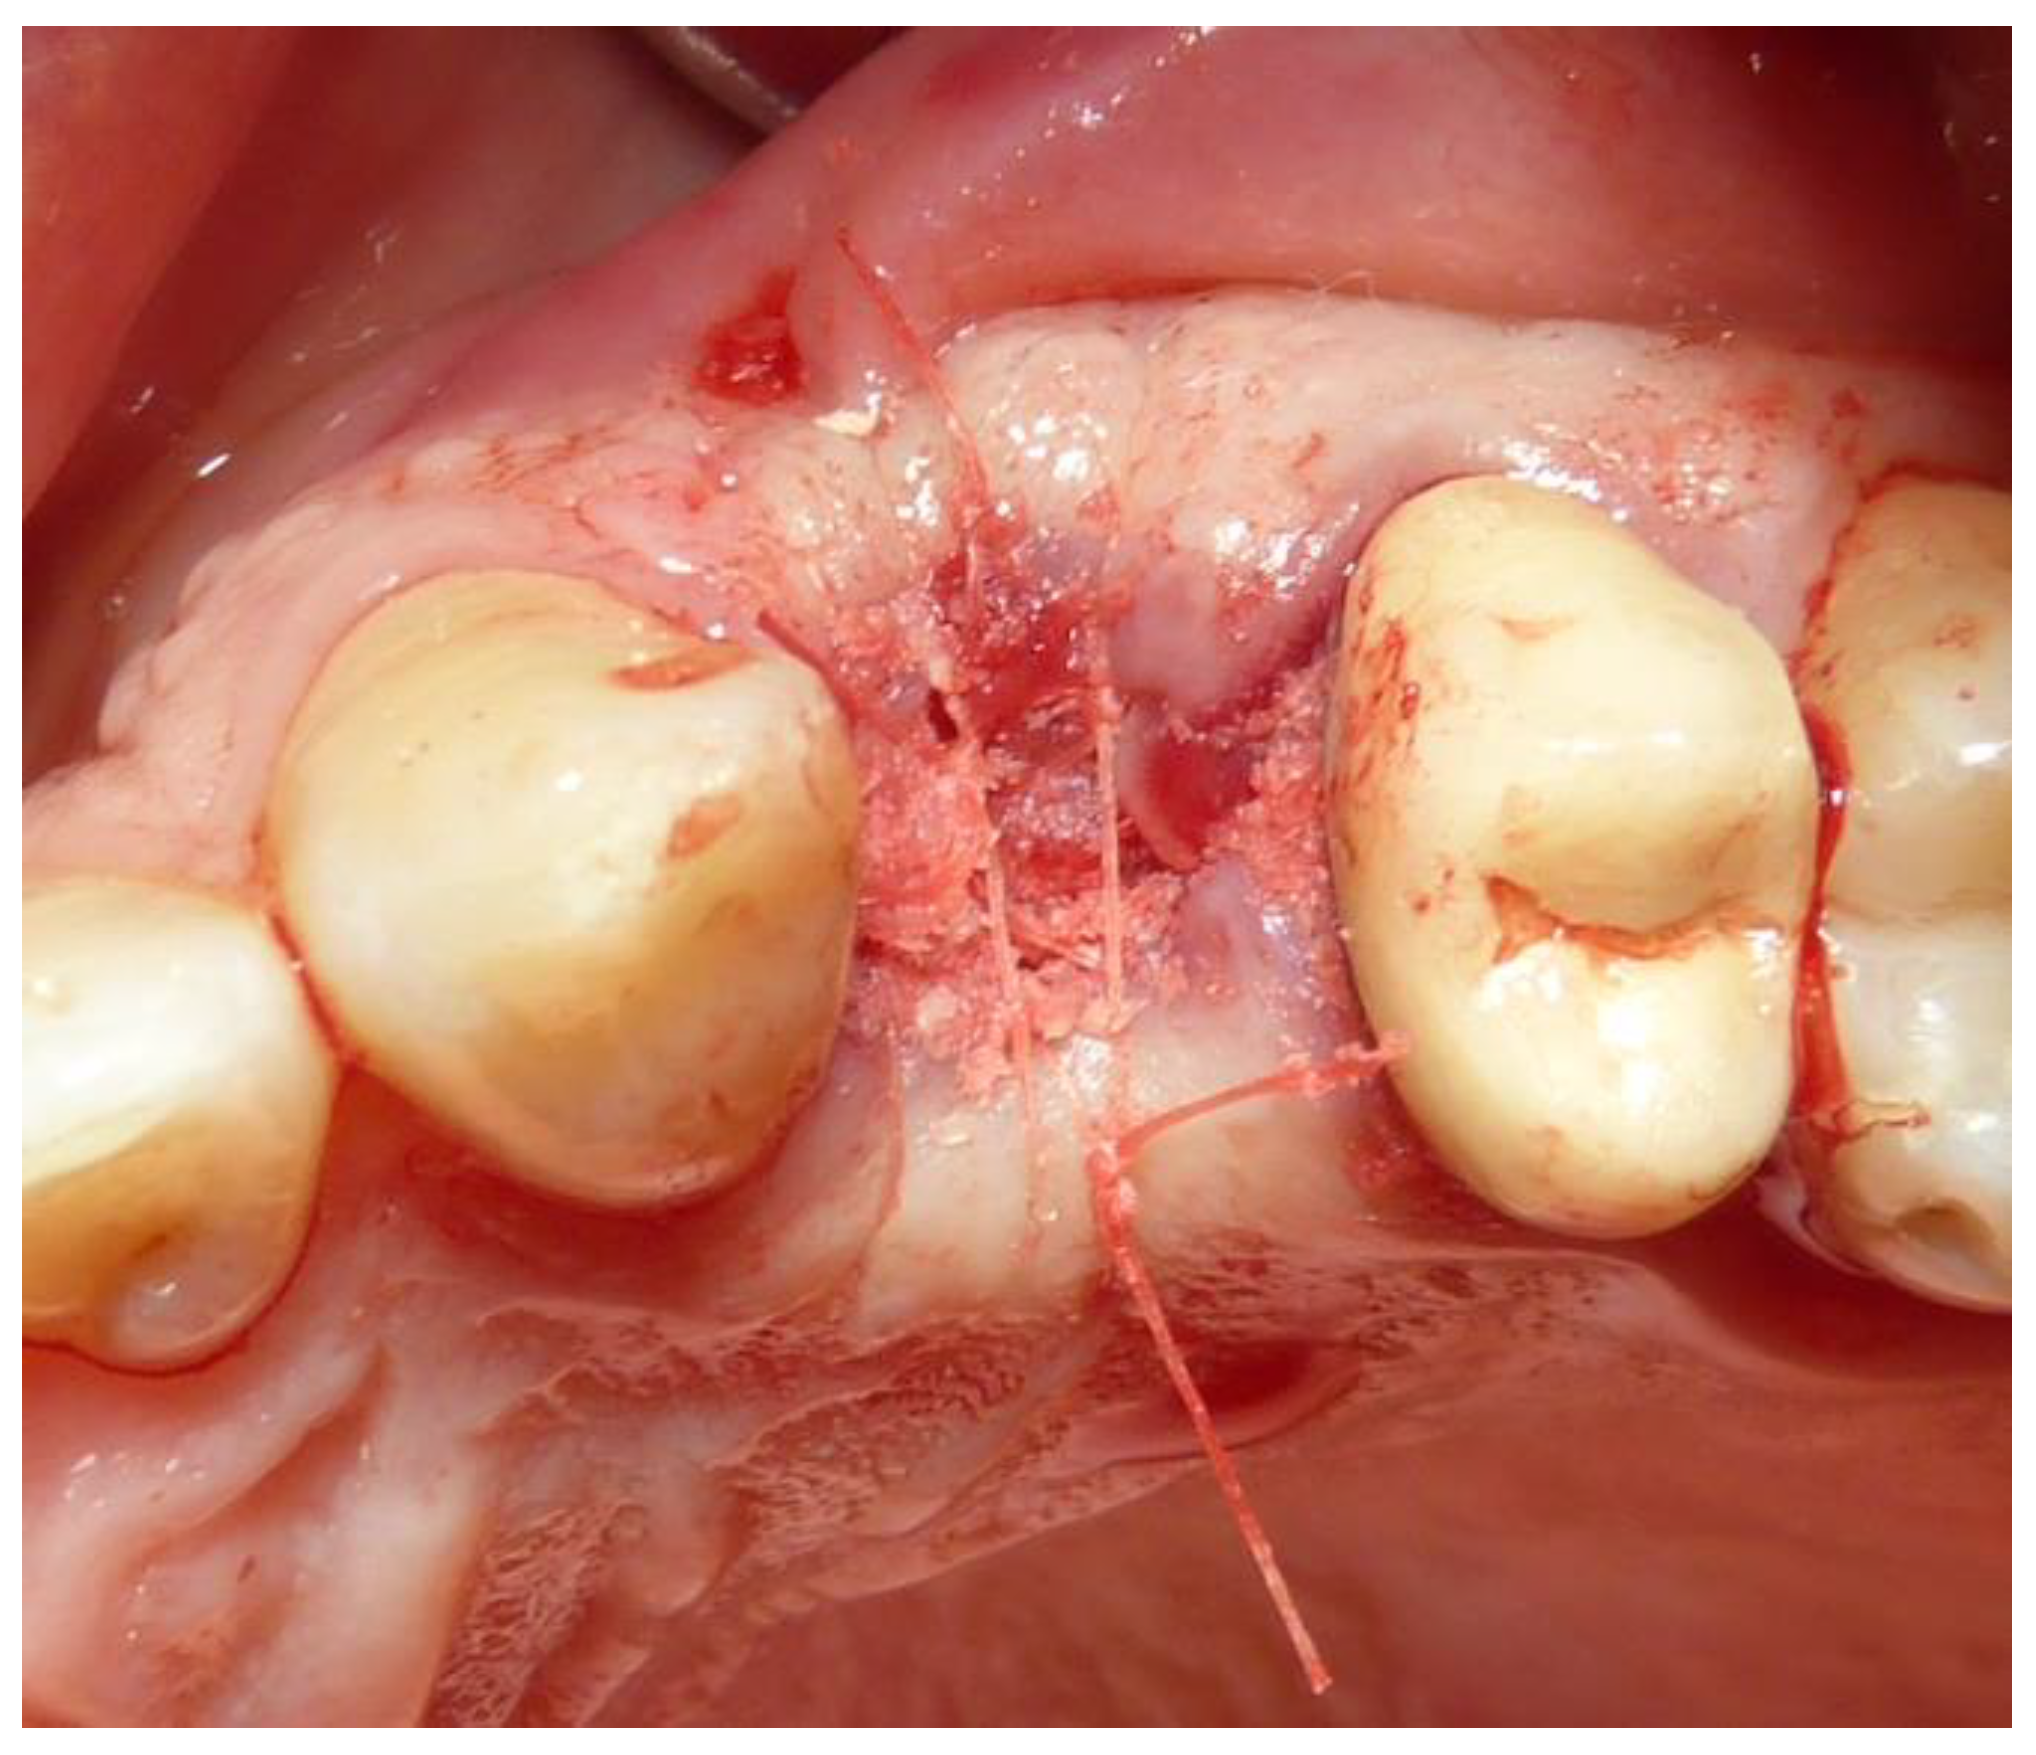

- Subjects who underwent surgical intervention for tooth removal and alveolar socket preservation using exclusively a tooth-derived bone substitute (Tooth Transformer®—Tooth Transformer SRL).

2.3. Preoperative and Surgical Procedures